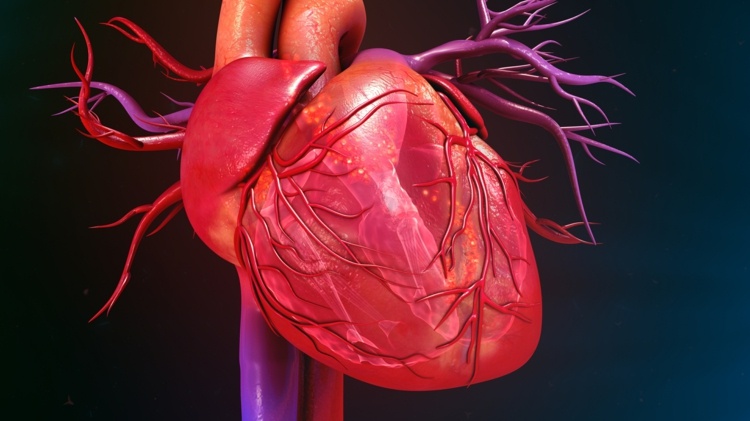

Umelé srdce prináša nádej pre tých, ktorí majú srdcové choroby – prvé pumpujúce umelé srdce zo silikónu

Po celom svete je nedostatok darcovských orgánov, a to platí najmä pre srdcia. Nečudo teda, že vedci stále viac pohrávajú s umelými srdiečkami, ktoré sa čo najviac približujú skutočnej veci. Nové orgány sa spravidla pestujú pomocou kmeňových buniek. Na prvé pumpovanie umelého srdca však doktorand Nicholas Cohrs použil 3D tlačiareň. Vývojár vytvoril umelé srdce, ktoré je v mnohých ohľadoch podobné ľudskému.

Aj keď je umelé srdce inak veľmi podobné ľudskému srdcu, okrem dvoch bežných srdcových komôr má ešte tretiu, ktorá je zodpovedná za pumpovanie. Tlak vzduchu tam napodobňuje svalové kontrakcie, ktoré zabezpečujú, že v tele môže prúdiť krv. Tím vedcov z ETH Zurich v tomto dosiahol veľký pokrok. Umelé srdce však zďaleka nie je vhodné na implantáciu.